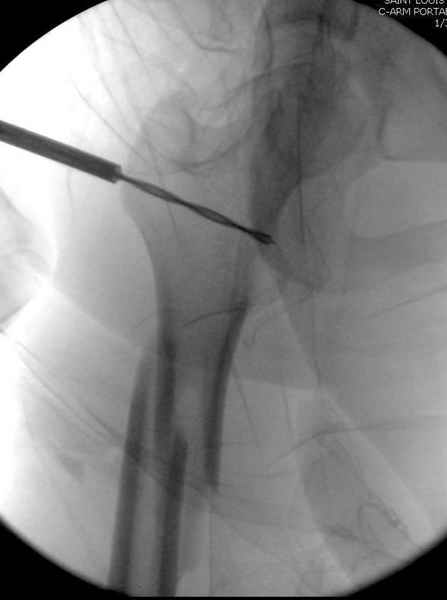

Как раз недавно у меня был примерный случай: больному 36 лет, поступил ночью, травма в результате мотоциклетной аварии, кроме чрезвертельного и спирального перелома левого бедра имеется переломы костей предплечья с этой же стороны. Скелетное вытяжение, а на следующий день больной про оперирован на ортопедическом столе с дистракцией. Чтобы не расколоть чрезвертельный перелом провели временную спицу ближе к переднему кортексу, из малого разреза костодержатель для репозиции, а фиксацию провели антиградным штифтом. Этапы операции на снимках.

Джолдас Кульджанов